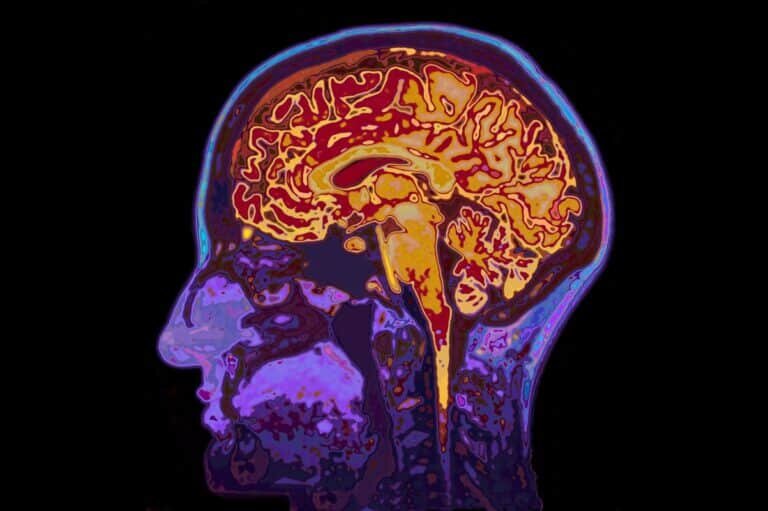

Ученые обнаружили, что длительное пребывание в условиях микрогравитации вызывает расширение желудочков головного мозга. На восстановление их обычных размеров уходит около трех лет после возвращения на Землю.

В нашем головном мозге есть полости — желудочки и каналы, заполненные спинномозговой жидкостью. Эта система защищает и питает нервную ткань, через нее удаляются отходы жизнедеятельности клеток. Длительное пребывание в космосе, в необычных для нашего организма условиях микрогравитации, заставляет желудочки адаптироваться и расширяться. По возвращении на Землю их восстановление занимает годы. К такому выводу пришли ученые из Университета Флориды, статья которых опубликована в журнале Scientific Reports.

Рэйчел Сидлер (Rachael Seidler) и ее коллеги проводили исследования 30 американских астронавтов, из которых восемь провели в космосе около двух недель, 19 — по шесть месяцев, четверо — около года. Краткие полеты участников первой группы почти не сказались на величине желудочков их мозга. Но начиная с шестимесячных миссий на орбиту эти полости у астронавтов существенно расширялись. При этом большой разницы между участниками полугодовых и годовых полетов не замечено: по-видимому, со временем процесс увеличения желудочков замедляется.

Любопытно, что на это расширение влиял и опыт прошлых полетов: 18 из исследованных астронавтов отправлялись в космос не впервые, и у тех, кто в очередной раз побывал там менее чем через три года после прошлых полетов, изменение размеров желудочков мозга было минимальным. Если же между миссиями проходило больше этого времени (в исследованной группе — от трех до девяти лет), желудочки снова начинали расширяться. Из этого ученые сделали вывод о том, что примерно за три года полости мозга восстанавливают свой обычный для земных условий размер.